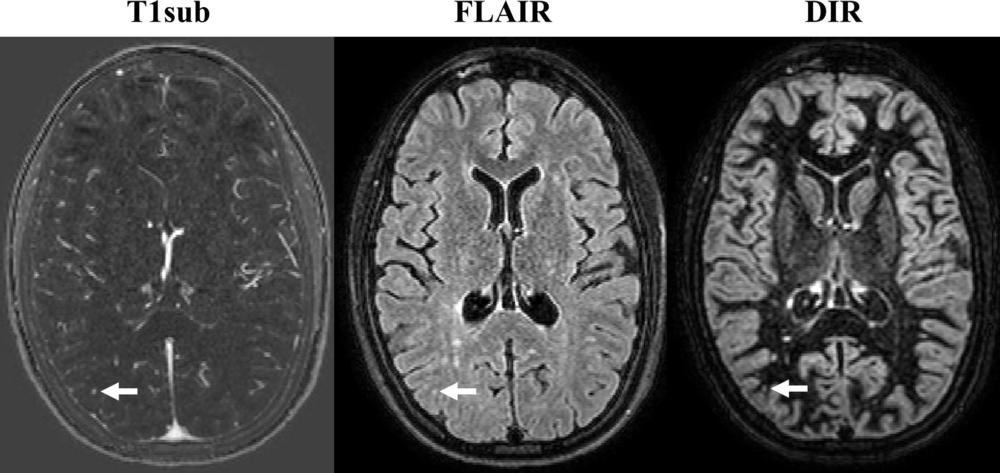

Dr. Wiestler credited an image subtraction pipeline developed and researched at his facility for the powerful sensitivity of the non-contrast MRI in detecting newly occurring lesions. The approach combines 3-D MRI and subtraction techniques, which cancel out unchanged areas in the follow-up image, substantially improving visualization of new or enlarging white matter lesions.

This combination of 3-D sequences and subtraction techniques is key to improving sensitivity for detecting newly occurred lesions, Dr. Wiestler said.